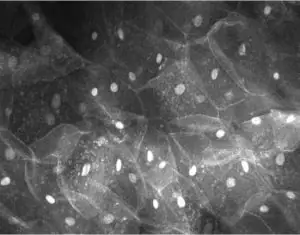

The Melbourne University Dental School and OptiScan are collaborating to improve the screening and early diagnosis of oral cancer, which affects 750,000 people around the

The University of Florida College of Dentistry (UFCD) and HT BioImaging Technologies are testing a new method for detecting premalignant and malignant oral lesions using